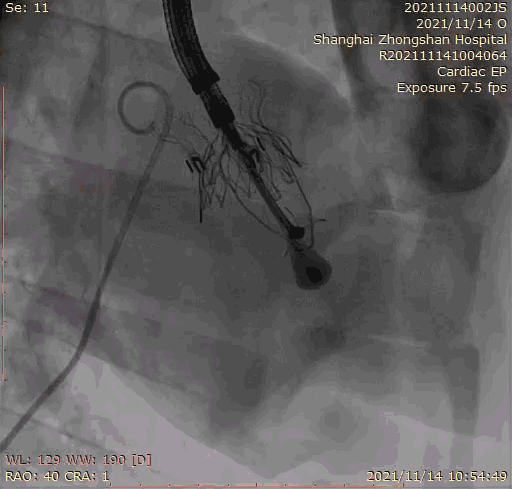

本次臨床前研究經(jīng)右側(cè)頸靜脈置入LuX-Valve Plus輸送系統(tǒng)可調(diào)彎鞘管,在DSA及超聲引導(dǎo)下將人工三尖瓣瓣膜植入到原有三尖瓣位置,利用獨特的錨定技術(shù)將人工瓣膜支架可靠固定在預(yù)定的位置。

Lux-Valve是全球第一款具有我國完全自主知識產(chǎn)權(quán)的經(jīng)導(dǎo)管介入三尖瓣置換系統(tǒng),利用前瓣夾持及室間隔錨定的復(fù)合方式進(jìn)行瓣膜裝置的固定,不依賴瓣環(huán)徑向支撐力,同時采用自適應(yīng)復(fù)合裙邊材料,有效的貼合密封柔軟的三尖瓣瓣環(huán),針對于三尖瓣返流的患者有優(yōu)異的療效。Lux-Valve Plus采用全新的經(jīng)血管輸送系統(tǒng),經(jīng)頸靜脈入路創(chuàng)傷更小,可以進(jìn)一步降低手術(shù)風(fēng)險。相信在后期正式臨床研究開展中,Lux-Valve Plus必定會為更多的三尖瓣反流患者帶來福音。